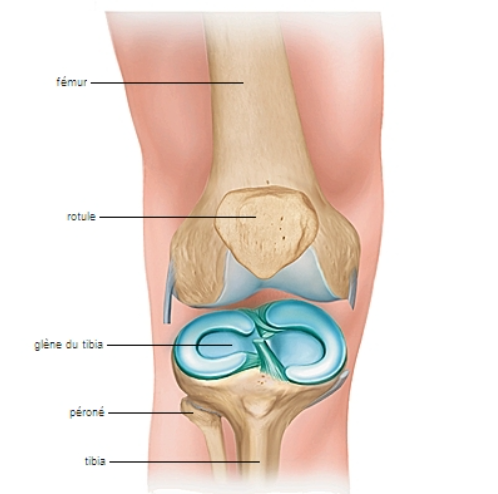

Les ménisques, en forme de croissant, sont des structures cartilagineuses situées dans le genou. Ils amortissent les chocs et assurent la stabilité de l’articulation. Cependant, ils sont fragiles face aux mouvements brusques ou aux torsions. Ainsi, ils peuvent se déchirer, surtout chez les sportifs ou lors de faux mouvements. Le Dr ALLAOUI Oussama Hamza prend en charge ces lésions et propose des traitements personnalisés pour préserver la fonction du ménisque et soulager la douleur.

Le traitement dépend de la gravité de la blessure. Dans certains cas, la rééducation, la physiothérapie et les mesures anti-inflammatoires suffisent. Cependant, les lésions plus importantes nécessitent une chirurgie, telle que l’arthroscopie, pour réparer ou retirer la partie endommagée du ménisque. Ensuite, une bonne rééducation et des exercices préventifs aident à limiter les risques de récidive et à retrouver une mobilité optimale du ménisque.